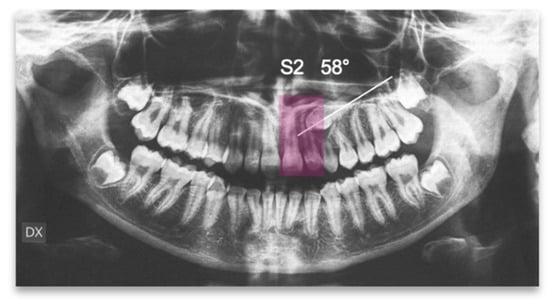

An 18-year-old female patient was referred, complaining of unpleasant smile. She presented good general health and no systemic or congenital diseases. From a frontal view, the patient presented a well-proportioned three-thirds of her face and no evidence of asymmetry. From the lateral view, the profile appeared convex with well-represented nasolabial angle, labiomental sulcus, and lip competence. Intraorally, the patient showed a Class II malocclusion with the molar Class I relationship, edge to edge canine relationship on both sides, increased overjet, overbite, and the retention of the 63. Panoramic, lateral headfilm, and dental cast records were taken (Figure 11).

Figure 11.

An 18-year-old female with dentoskeletal Class II with impacted upper left canine before treatment.

The initial cephalometric analysis showed a skeletal Class I relationship (ANB, +2.6°) and mesodivergent pattern with the proclination of the upper (I/ANS-PNS 118.8°) and lower (i/GoGn:102.2°) incisors. All the radiographic findings, the age of the patient, the prolonged deciduous retention, and the risk of root resorption of the adjacent tooth, led clinicians to conclude that the permanent canine would not erupt properly without intervention (Table 2).

The position of the impacted canine showed an alpha angle of 58° and the Ericson and Kurol II sector classification. No clinical symptoms on articular examination were detected (Figure 12).

Figure 12.

Pre-treatment panoramic X-ray with the evaluation of alpha angle and sector according to the Ericson and Kurol classification.